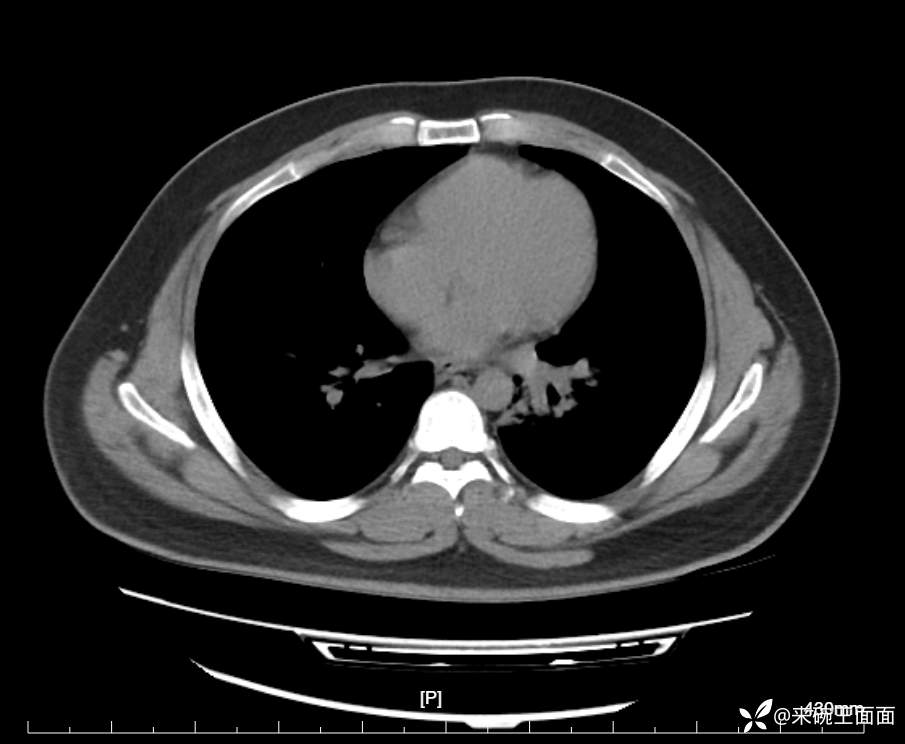

性别:男

年龄:27岁

主诉:胸闷胸痛数月余,休息后可自行缓解,无咯血症状。

个人史:数年吸烟史,具体不详。